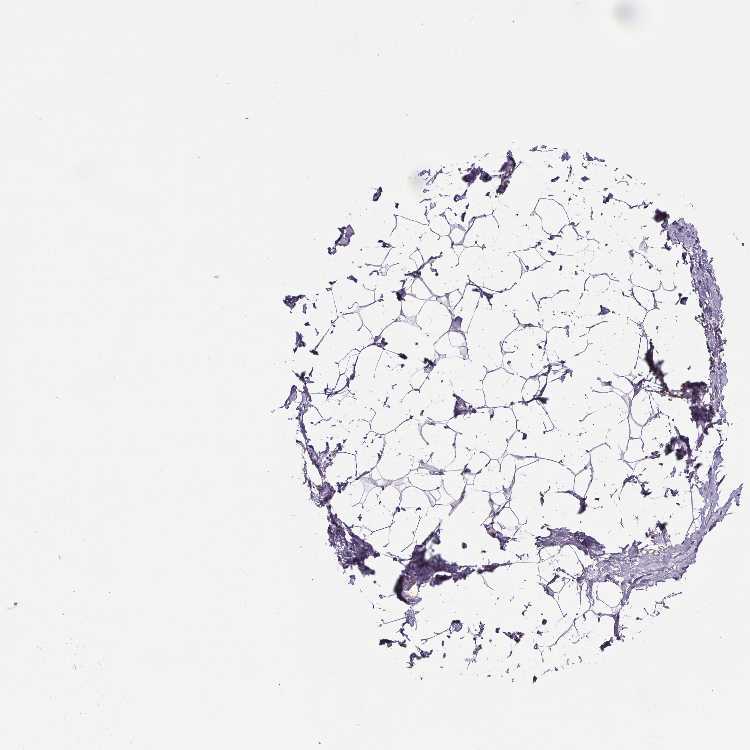

BREAST - Antibody stainingi

Antibody staining in the annotated cell types in the current human tissue is reported as not detected, low, medium, or high, based on conventional immunohistochemistry profiling in selected tissues. This score is based on the combination of the staining intensity and fraction of stained cells.

Each image is clickable and will lead to virtual microscopy that enables deeper exploration of all samples and also displays staining intensity scores, fraction scores and subcellular localization as well as patient and tissue information for each sample.

Antibody HPA004133Antibody HPA043854

Adipocytes Not detectedNot detected

Glandular cells Not detectedNot detected

Myoepithelial cells Not detectedNot detected